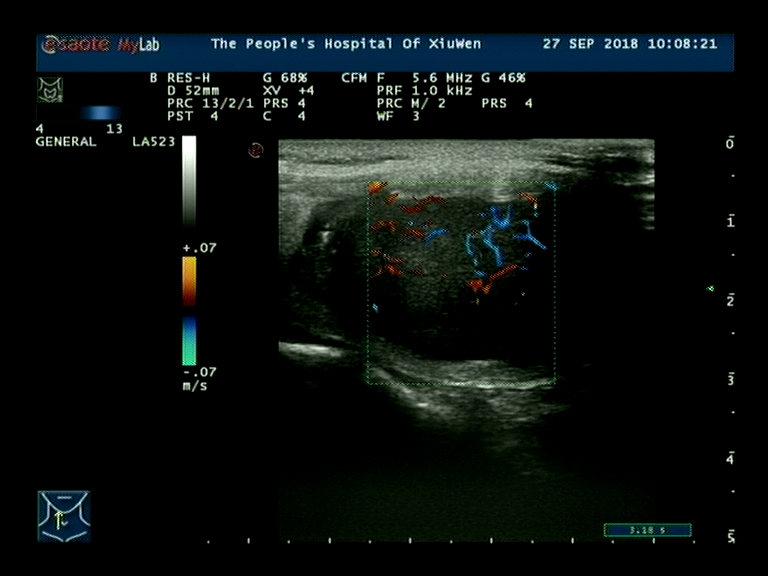

超声

超声表现:低回声结节,水平位椭圆“躺蛋样”,周围声晕厚薄不均,CDFI内部及周边血流丰富、紊乱;TR—4b类。

MTC超声表现:多位于甲状腺中上极,这是因为滤泡旁C细胞主要位于中上极;散发性者多为单发,遗传性者多为双侧多发;结节相对较大,多具有规则的边缘,更易呈现为卵圆形,纵横比多<1,呈“躺鸡蛋”样;钙化发生率相对较低,且粗钙化发生率较高,较PTC的钙化灶更致密、更粗糙;CDFI多为高血供;发生淋巴结转移的几率高于PTC,转移淋巴结的回声与原发灶接近,且两者钙化表现一致,呈“子母瘤”样改变。值得注意的是,部分MTC无显著恶性征象:形态规则,边缘光整,边界清晰,无钙化,容易误诊。还应注意的是,部分MTC的超声表现与甲状腺腺瘤类似,都表现为单发性类圆形低回声结节;但两者存在不同之处:① 髓样癌多位于腺体中上部,钙化发生率较高:② 髓样癌多无包膜,而腺瘤则有完整包膜;③ 髓样癌边缘的声晕不完整、厚薄不一,而腺瘤的声晕则完整、厚度均一;④ 髓样癌内部及周边血流丰富、紊乱,而腺瘤则多为环状血流,血管走行规则。CT表现为甲状腺内形态不规则、边缘不清肿物,可见不均匀强化伴内部不规则低密度区,部分可见点状或圆形钙化,增强扫描多明显强化。淋巴结转移多见,表现为与原发肿瘤一致的不均匀强化背景下低密度区。临床工作中,出现此类表现的甲状腺肿物患者,如降钙素显著升高,应考虑MTC的可能,确诊需结合病理及免疫组化,此外应全面检查除外其他部位的远处转移。微小MTC的影像学表现与非微小MTC有很多相似之处,如实性、低回声、钙化、无声晕、血供丰富等,但也具有一定的特别征象,如形态不规则等,后者极易与微小PTC混淆。与超声比较,CT在微小MTC显示、判断上不及超声检查。